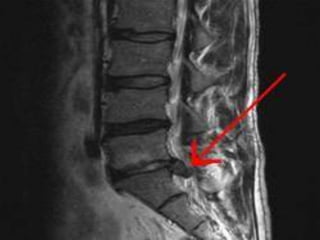

MRI lumbar spine;

 Helps to visualize the disc, nerve root, thecal sac.

 Compression of nerve root.